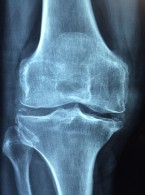

Ocena stanu przyzębia pacjentów z reumatoidalnym zapaleniem stawów, leczonych klasycznymi lekami modyfikującymi przebieg choroby, i zapaleniem przyzębia

Zobacz więcej

Assessment of periodontal status in patients with rheumatoid arthritis treated with disease-modifying anti-rheumatic drugs and periodontitis

Tomasz Kaczyński, Jakub Wroński, Bartłomiej Górski, Piotr Głuszko, Artur Rasiński, Renata Górska